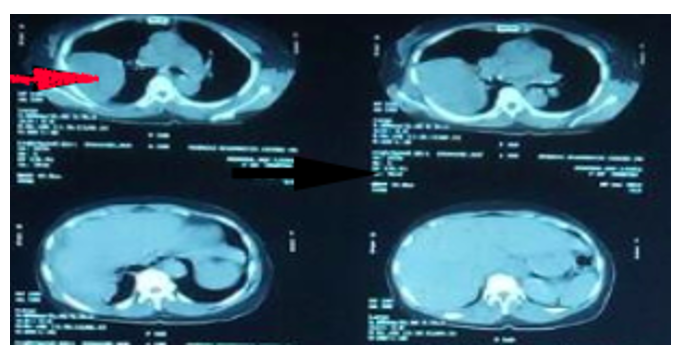

CT Imaging of Pancreatitis and its Complications

Farheen Raza and Muhammad Mobeen